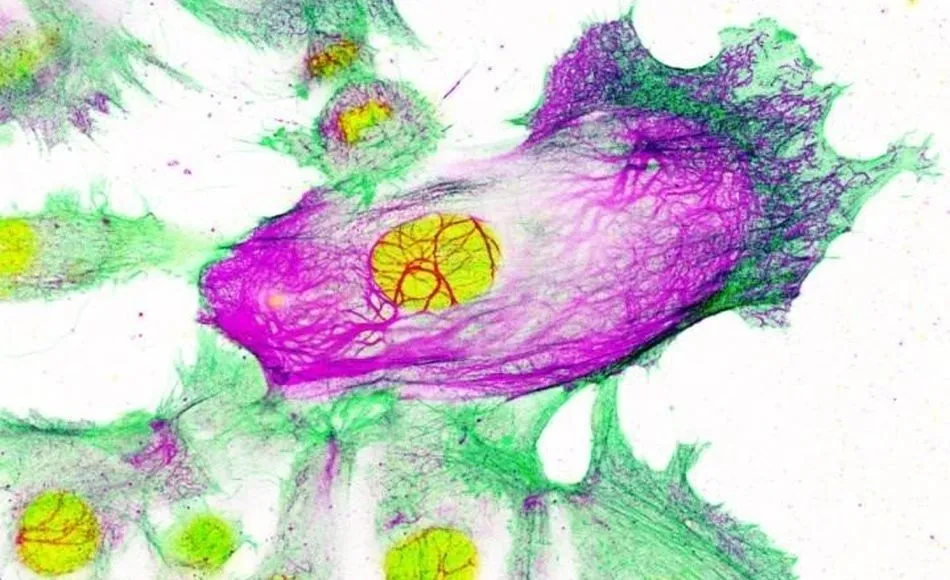

Este hallazgo, que se acaba de publicar en la revista 'Nature Communications', han descubierto que la enzima FASN, cuyos niveles se encuentran elevados en numerosos tipos de cáncer, es crucial para que se produzca uno de los procesos esenciales por el cual una célula normal se transforma en cancerosa. Bloquear FASN en un modelo animal de cáncer de mama agresivo retrasó la aparición de tumores y amplió su supervivencia en un 68 por ciento.

El equipo ha trabajado para desarrollar este proyecto con el Hospital de Fuenlabrada, Quirón de Pozuelo y el Hospital de la Princesa. En esta investigación se ha podido demostrar que cuando las células no tienen FASN, un complejo de proteínas implicadas en la síntesis de ácidos grasos, no son capaces de realizar uno de los pasos más importantes para que se formen tumores: normalmente las células de los tejidos sanos crecen en capas, bidimensionales, y cuando se amontonan suelen morir. La capacidad de amontonarse y crecer en aglomerados es una de las características de los tumores.

El grupo del doctor Quintela ha comprobado que las células sin FASN no son capaces de dar este paso fundamental en el desarrollo del cáncer. No solo eso, sino que modelos animales en los que se elimina FASN no llegan a desarrollar tumores. El bloqueo de este mecanismo ha retrasado la aparición de tumores y ampliado la supervivencia un 68 por ciento. Aunque la interrupción de la función de FASN no elimina tumores ya establecidos, estos datos tienen muchísima importancia en el campo de la prevención del cáncer de mama, abriendo una vía nunca explorada hasta el momento.